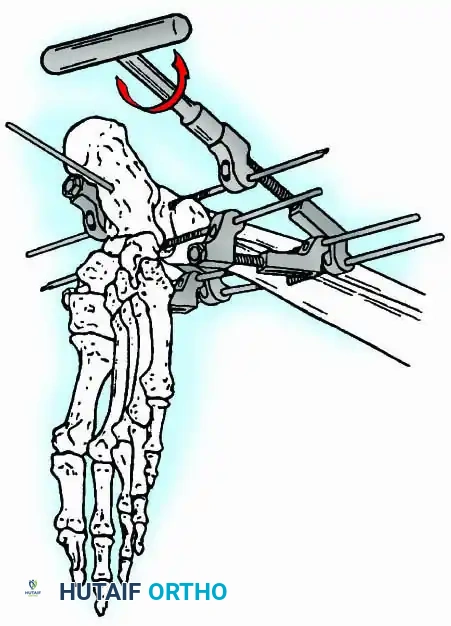

Modern iterations, such as the Calandruccio II compression device, offer greater latitude in pin placement to avoid compromised skin. Ring or circular external fixators (Ilizarov, Taylor Spatial Frame) are the gold standard for salvage situations, including active infection, massive bone loss, or failed TAA, as they allow for simultaneous compression, deformity correction, and early weight-bearing.

In cases of severe osteopenia or when extending the fusion to the subtalar joint (Tibiotalocalcaneal Arthrodesis), retrograde intramedullary nailing provides a load-sharing construct with superior bending stiffness.

Knee Arthrodesis

While total knee arthroplasty (TKA) is the definitive treatment for knee osteoarthritis, knee arthrodesis remains a critical salvage procedure. The primary indications are a chronically infected TKA that has failed two-stage revision, massive extensor mechanism disruption, severe neuropathic arthropathy, and tumor resection.

Positioning and Technique

The optimal position for knee arthrodesis is 10 to 15 degrees of flexion and 5 to 7 degrees of valgus. This slight flexion assists in foot clearance during the swing phase of gait and makes sitting in confined spaces more manageable. A perfectly straight (0 degrees) knee is cosmetically awkward and functionally detrimental, causing a vaulting gait pattern.